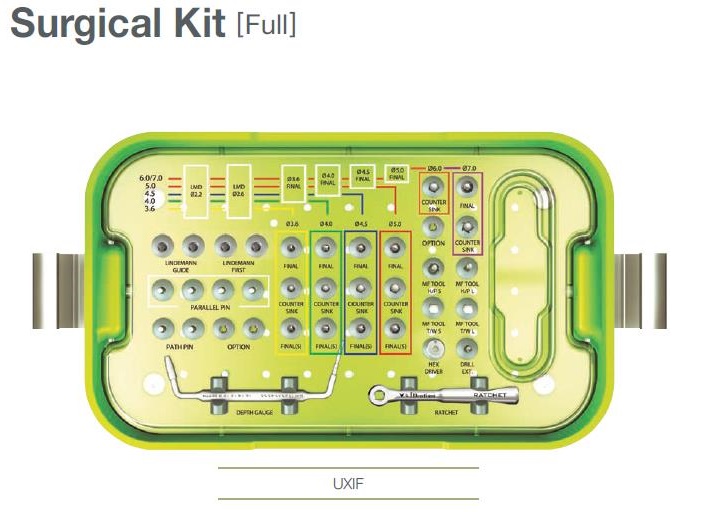

Не только от макродизайна импланта зависит то, как он себя ведет. Прежде, чем поставить имплантат, мы должны подготовить подготовить для него лунку, а для этого нам требуется специальный набор инструментов, т. н. kit.

Разные производители по-разному подходят к формированию набора инструментов. Так, например, компания Dentium выпускает два отдельных набора, один для хирургов:

другой — для протезирования:

Другая сторона — это сам хирургический протокол. В большинстве имплантационных систем он устроен примерно одинаково: от меньшего размера к большему. Однако, некоторые производители его настолько усложняют, что новичку в нем интуитивно не разобраться. Таков, например, хирургический протокол установки имплантов Astratech:

разумеется, это влечет за собой увеличение количества инструментов и усложнение хирургического набора:

Безусловно, когда вы уже десять лет ставите импланты Astratech, такое усложнение не играет для вас большой роли, но у имплантолога, впервые столкнувшемуся с подобной системой, установка импланта Astratech вызовет определенные трудности.